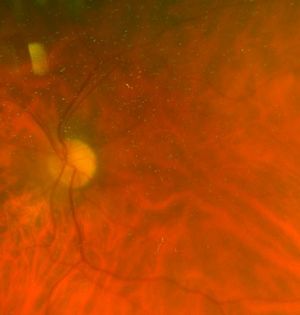

Foveal hypoplasia is commonly seen with conditions such as albinism, nystagmus, achromatopsia, iris abnormalities like aniridia, cataracts, and other ocular abnormalities.[32] Histologic analysis and OCT studies have revealed that the structure of the macula resembles peripheral retinal tissue with the persistence of ganglion and nuclear layers.[1][31] Ophthalmoscopy shows the absence of the foveal pit and FAZ.[2][4][9] Most patients with foveal hypoplasia have poorer than normal visual acuity ranging between 20/50 to 20/200.[9][32]

Historically, the diagnosis of foveal hypoplasia was made in nystagmus evaluation with the ophthalmoscopic examination of the fundus. Findings commonly included the absence of foveal pigmentation and the foveal reflex.[6][9] Introduction of fluorescein angiography allowed for visualization of the FAZ, and a small or absent FAZ coupled with ophthalmoscopy support the diagnosis of foveal hypoplasia.[9] Non-invasive imaging such as OCT and OCT-A (optical coherence tomography angiography) are now commonly used to evaluate the morphology and vasculature of the retina, respectively. In foveal hypoplasia, OCT evaluation reveals the absence of the foveal pit and the persistence of inner retinal layers through the area where the foveal center is expected.[2][32] OCT-A evaluation of the FAZ shows an absence at the superficial capillary plexus and a variable decrease in the deep capillary plexus.[33][34]